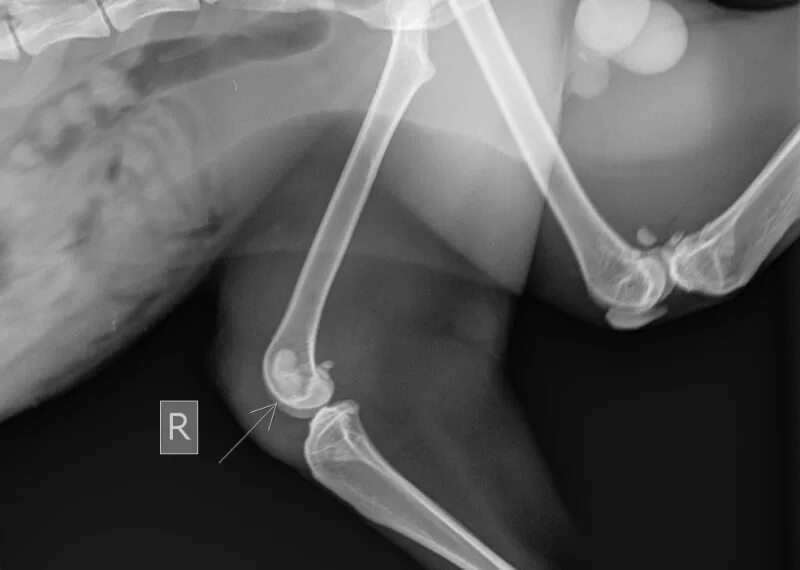

Связка кошек